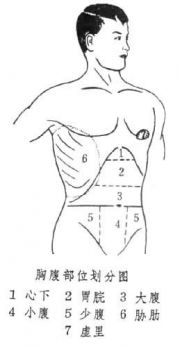

| 2021年7月26日 (一) 20:03 | 胸腹部位划分图.jpg (文件) |  |

24 KB | Uploaded with SimpleBatchUpload | 3 |